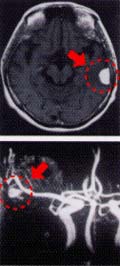

人間ドックをお受けの際「人間の人間たる」由縁である崇高な脳についてもドックをお受けください。 最新鋭のMRI 1.5T(核磁気共鳴装置)を使い、痛みも無く安全に脳ドックが 可能になりました。MRI検査では脳そのものを画像化し、脳梗塞や脳腫瘍(写真上)の早期発見が可能です。 また、同装置を用いたMRA検査では脳の血管が描き出され、クモ膜下出血の原因となる脳動脈瘤(血管のコブで 破れやすい、写真下)や動脈硬化の程度が分かります。生活習慣病の代表である「脳卒中」を未然に防ぎ、 健康な生活を楽しんでください。